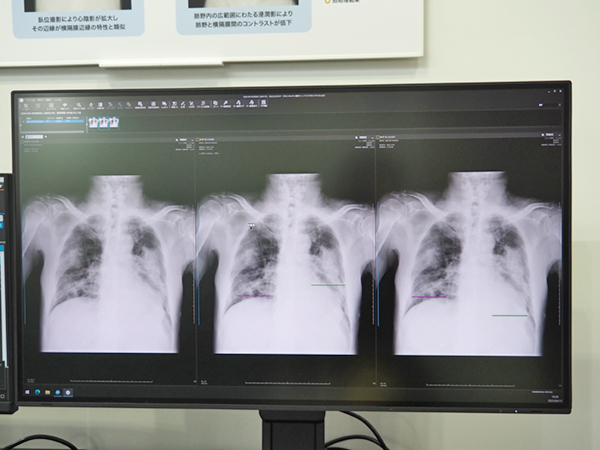

KINOSISの機能は年々増加しており,AIを活用した技術は「気管径測定機能」(TD-MODE)がすでに搭載されている。TD-MODEでは,AIが肺野内の構造物の大きさの経時変化を可視化し,呼気周期時の気管径狭小化について変化率・変化量から観察できる。さらに,現在開発中の技術として「横隔膜同定技術」が紹介された。このうち横隔膜同定技術は,救急での動態回診撮影などでも病変やデバイスの影響を受けにくく,横隔膜を追跡・定量化する技術である。臥位撮影で心陰影が拡大した症例や肺野内の広範囲にわたる浸潤影により肺野と横隔膜間のコントラストが低下した症例などでも横隔膜を正確に同定し,横隔膜の変化を定量的に評価できる。

現在開発中の「横隔膜同定技術」